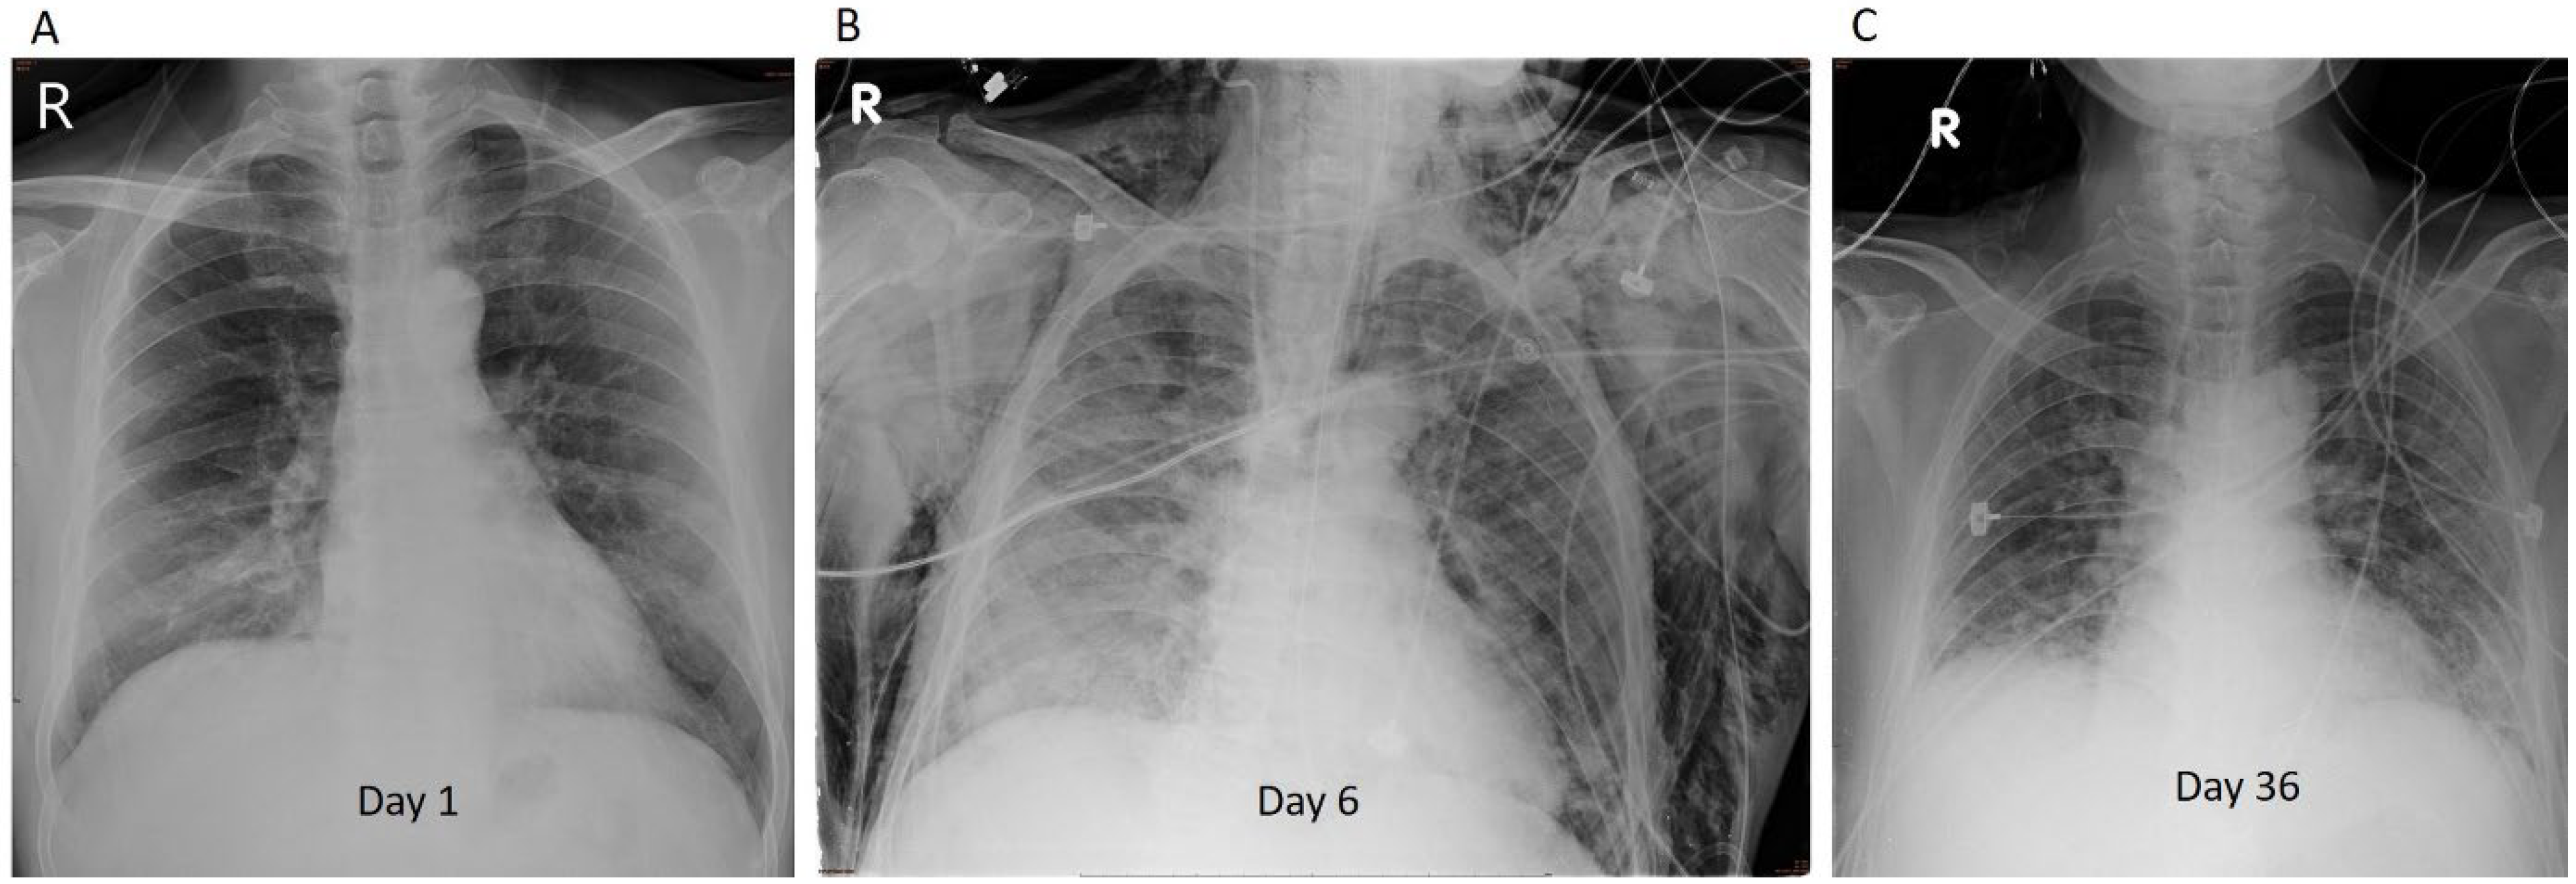

2.2. Representative Case 2 (Patient 5)